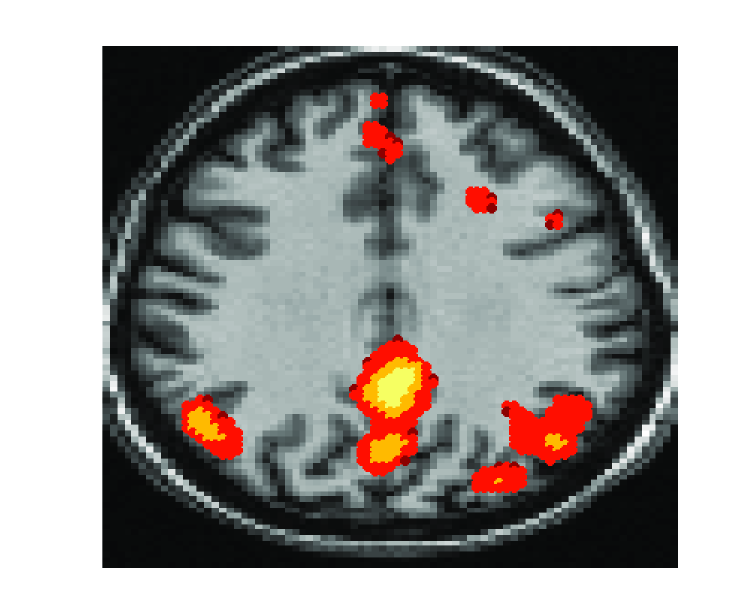

• [28]  , Non-orthogonal joint diagonalization in the least-square sense with application in blind source separation, IEEE Transactions on Signal Processing, 50 (2002), pp. 1545–1553.